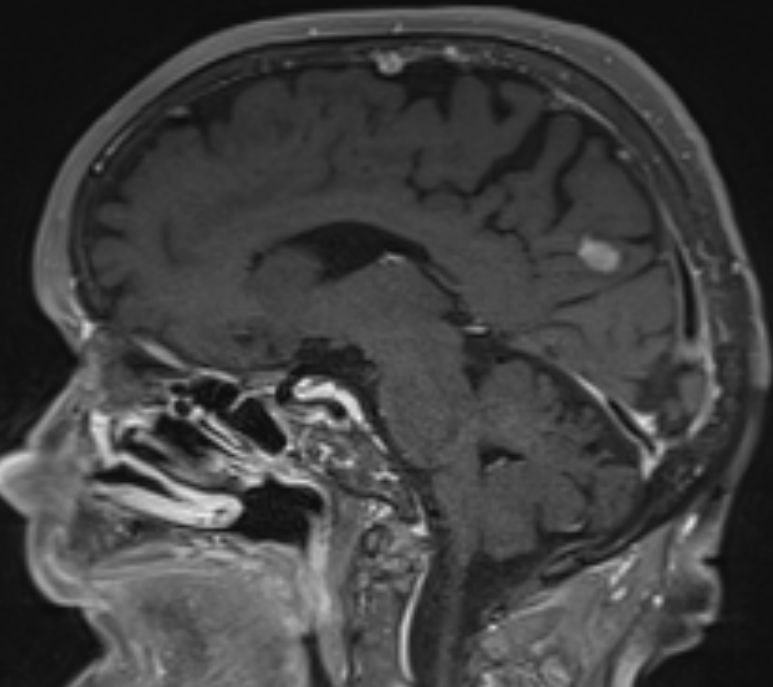

84-jährige Frau, die vor 3 1/2 Jahren einen 35 mm großen derben

Rektumpolypen entwickelte. Die submuköse Exzision ergab ein malignes Melanom

mit Infiltration der tiefen Muskulatur und Ummauerung größerer Gefäße. BRAF+.

Vor 2 Jahren Rektumschleimhau-Rezidiv und Metastase rechts pararektal:

anteriore Rektumresektion. Vor 4 Monaten Lungenmetastase und singuläre

Hirnmetastase re occipital. Dabrafinib + Trametinib nach 2 Zyklen wegen

Hepatotoxizität und Hautausschlag abgebrochen. Jetzt: RT der Hirnmetastase

und des pararektalen Tumors. |